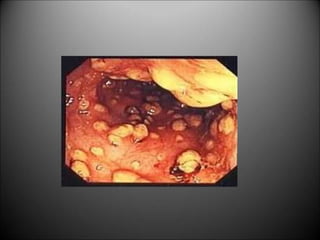

PSEUDOMEMBRANOUS COLITIS

Cl. Difficile

Overtakes normal flora in patients on antibiotics

Watery diarrhea, abdominal pain, fever

Sigmoidoscopy: membrane of exudates (pseudomembranes)

Stool- culture and toxin assay

Treatment :

stop offending antibiotic

oral vancomycin/ metronidazole

rehydration, isolate patient